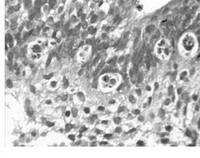

В реакции иммунофлуоресценции в срезах эндометрия наблюдалось очаговое и диф¬фузное свечение (++++ и +++) макрофагов и лимфо¬ци¬тов, инфильтрирующих строму эндо¬мет¬рия. ГАМК+ реакцию проявляли также отдельные межэпителиальные лимфоциты же¬лез. Особенно заметно скопление ГАМК+ ли쬬фо¬ци¬тов с интенсивным диффузным свечением в периваскулярных инфильтратах. Сле¬дует выделить высокую иммуно¬реак¬тив¬ность эндотелиальных клеток мелких венул (рис. 2), отдельных артериол и лимфатических сосудов (рис. 3).

Рис. 2. ГАМК в эндотелиоцитах в венуле с высоким эндотелием. Непрямая реакция иммунофлуоресценции с анти-ГАМК моноклональными иммуноглобулинами (Dia Sorin, USA). Об. х40, гомаль х3

Максимально интенсивную люминесценцию (++++) проявляли эндотелиоциты венул с высоким эндотелием, преимущественно в эн¬до¬метрии с признаками активации вос¬пали¬тель¬ного процесса. Эндотелий здесь вы¬делялся диффузным, гомогенным ярким све¬че¬нием. При этом клетки часто проли¬ферировали, суживая просвет сосуда, имели набухшую, сочную цитоплазму и крупное ядро. По сравнению с контролем, интенсив¬ность люминесценции посткапиллярных венул при активном воспалительном процессе была больше выражена. В эндометрии, где воспа¬ле¬ние не отличалось активностью и на фоне склероза и ангиоматоза ткани, ГАМК+ поло¬жительные сосуды обнаруживались реже. При этом уменьшение числа иммунореактивных венул среди большого количества расширен¬ных сосудов с уплощенными эндотелиоцитами в очаге воспаления следует считать показа¬телем их функциональной неполноценности [10].